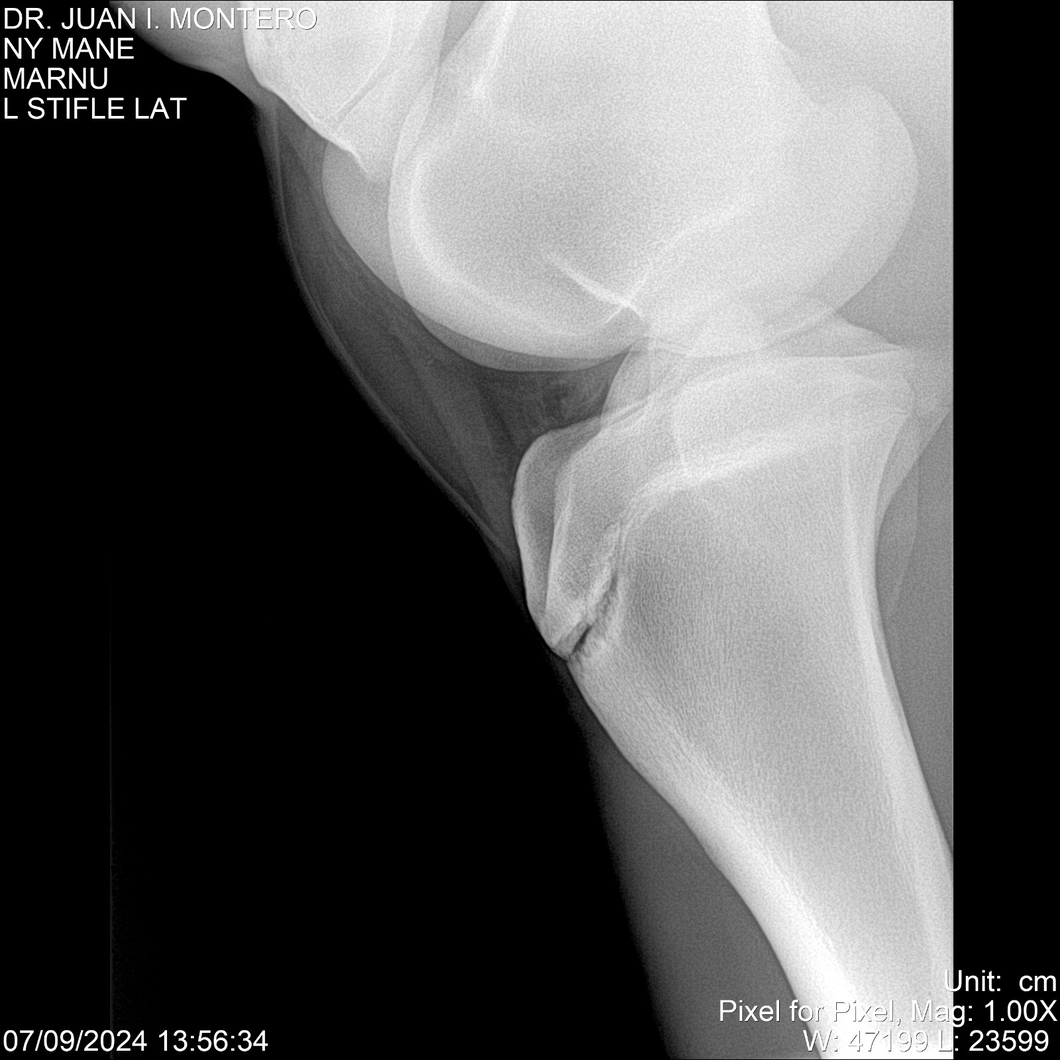

LOTE 20, NY MANE Lote Anterior Volver al remate Lote Siguiente Ficha Contacto Montevideo - Ficha del Lote Identificador: #282520 Categoría: Yeguarizos 76 Visualizaciones ClicData Contacto Empresa: Abelenda N. R., Walter Hugo Nombre*: Teléfono* : E-mail* : Mensaje Enviar Registrese gratis Este contenido Exclusivo está disponible sólo para usuarios registrados Ingresar